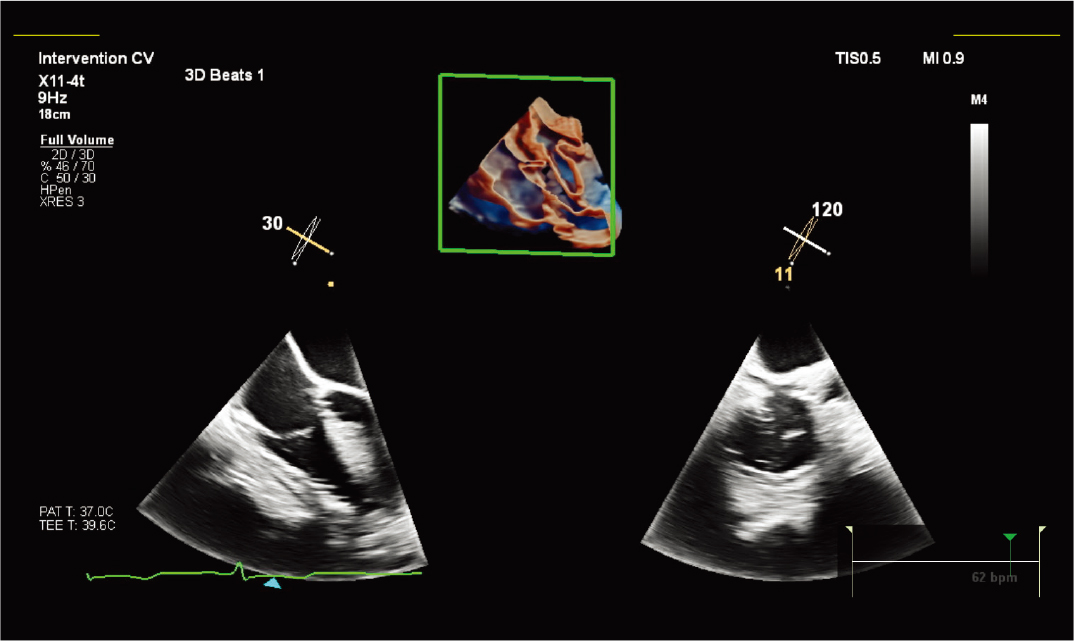

X11-4t 探头进行儿科左心耳评估 |

X11-4t 探头和 TrueVue 进行瓣下膜检查 |

X11-4t 探头和 TrueVue Glass 进行三尖瓣 MPR 成像。 |